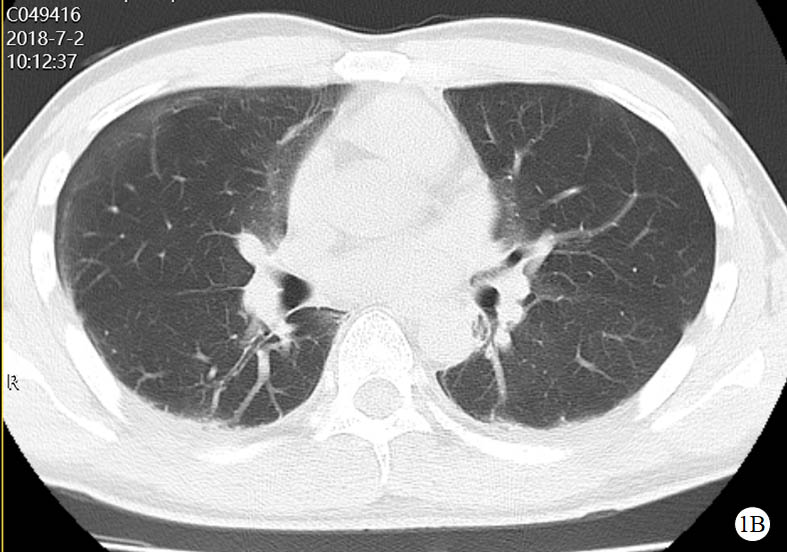

图 1 患者口服百草枯后胸部CT影像学变化

2018-07-02 CT图